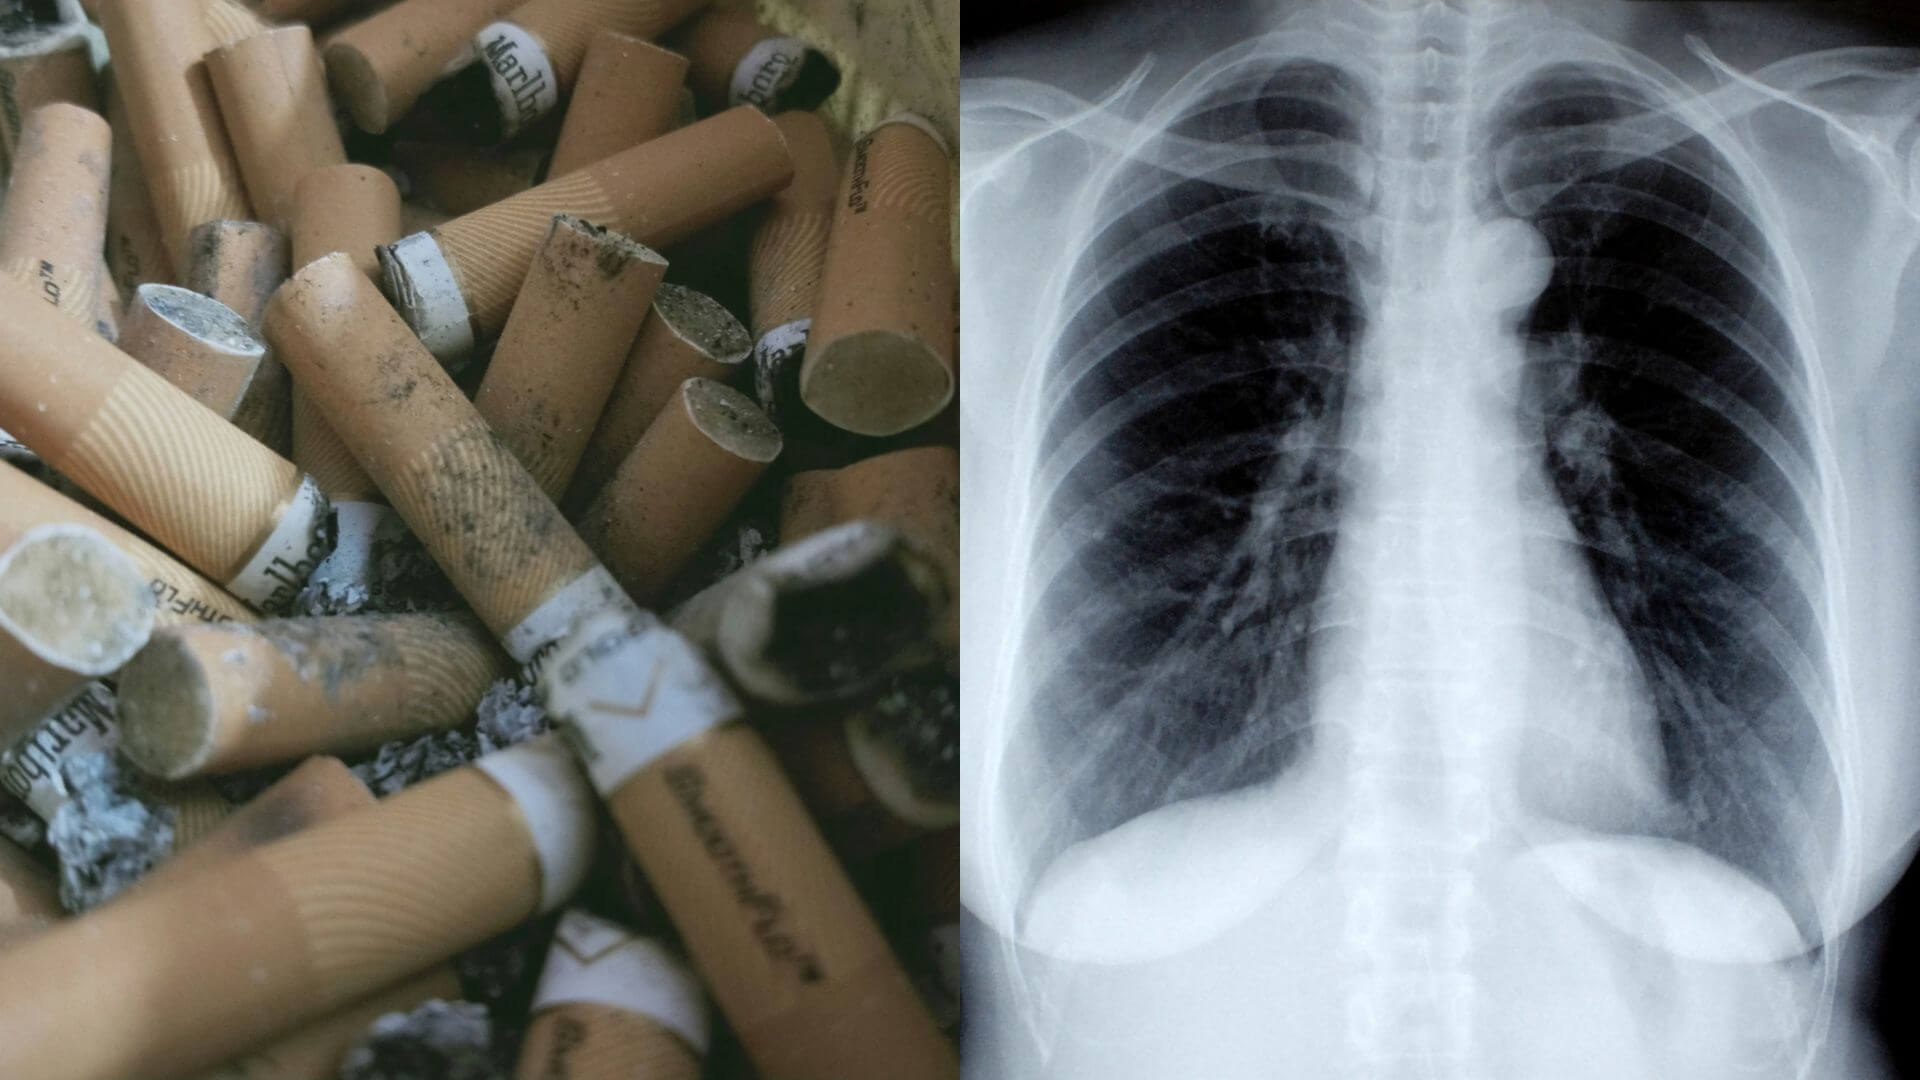

Ľudia, ktorí fajčia, majú najväčšiu šancu dostať rakovinu pľúc. Riziko rakoviny pľúc sa zvyšuje s dĺžkou času a počtom vyfajčených cigariet. Prestať fajčiť, aj keď fajčíte dlhé roky, výrazne znižuje šance na rozvoj rakoviny pľúc. Rakovina pľúc sa môže vyskytnúť aj u ľudí, ktorí nikdy nefajčili.

Fajčenie

Riziko rakoviny pľúc sa zvyšuje s počtom cigariet, ktoré každý deň vyfajčíte. Vaše riziko sa tiež zvyšuje s počtom rokov, ktoré ste fajčili. Odvykanie v akomkoľvek veku môže výrazne znížiť riziko vzniku rakoviny pľúc.

Vystavenie pasívnemu fajčeniu

Aj keď nefajčíte, riziko rakoviny pľúc sa zvyšuje, ak ste v blízkosti ľudí, ktorí fajčia. Dýchanie dymu vo vzduchu od iných ľudí, ktorí fajčia, sa nazýva pasívne fajčenie.